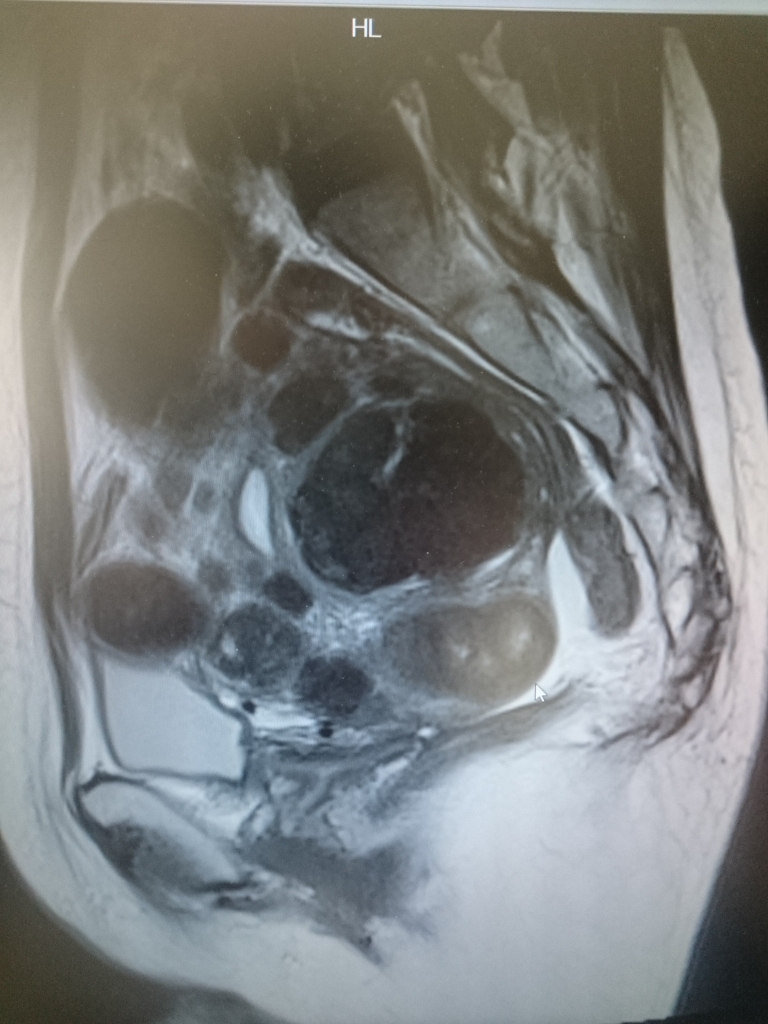

JUGEMテーマ:女性の病気 3月20日に心斎橋のクリニックで西区のN病院への紹介状を書いてもらってから 予約が取れたのが約1カ月後の4月26日。 1年半前に撮ったMRIのCDを引っ提げて、F先生の元へ・・・ F先生は画像を見るなり、「わぁーいっぱいあるやんかー。まぁ膀胱はあんまり圧迫 してないみたいやけど、生理多いんとちゃう?」 「手術したくないの?まぁそれはすぐ決めんでも考えたらいいけどね・・・ 比較的筋腫のある人は閉経が遅かったりするから・...

JUGEMテーマ:女性の病気 現在私は51歳(こないだ誕生日を迎えたばかり)、これまでの生涯未婚、出産経験なし。 長く付き合ってる彼氏はおります。 子宮筋腫が見付かったのは10年程前。 40歳を過ぎれば、4人に1人筋腫持ちってぐらいありふれた病気だし、通院していた 心斎橋のクリニックでも「年齢からして閉経した小さくなるし、様子を見ましょう。 1年に1回は大きくなっていないか検査に来てね」な程度だったので。 放置。 健康診断で2年に1回の婦...

JUGEMテーマ:女性の病気 2018年11月2日、子宮筋腫による貧血、生理の出血多量、下腹部の張りから 解放されるために、子宮全摘出しました! 同じようなブログは多々ありますが、人によって症状や術式、術後の体調は 千差万別ですので、私の場合を記録しておきます。 これから手術を考えられている方の参考になればうれしいです。